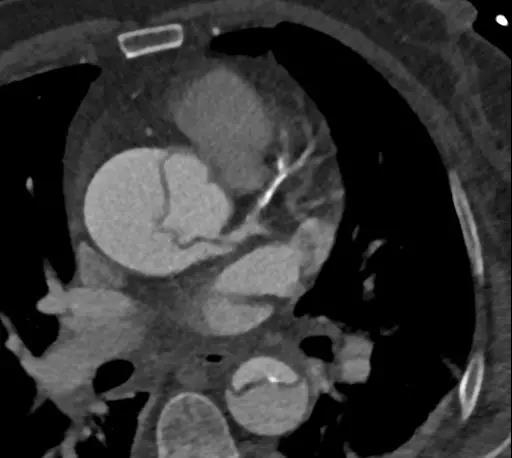

图1:夹层累及左冠状动脉的典型图像

虽然,患者的确发生了心梗,但是原因并非冠心病,而是因误诊而服用的阿司匹林和氯吡格雷让我们无法急诊手术,只能等......等到手术的出血风险变小时,再奋力一搏!然而,主动脉夹层48小时内死亡率高达50%